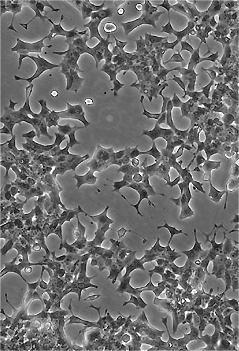

RIN-m5F

RIN m5F; Rin-M-5F; Rin-m-5F; RINm-5F; RINm5F; RIN Cl-5F

90%RPMI-1640+10% FBS

Temperature: 37°C ; Carbon dioxide (CO₂), 5%

贴壁细胞